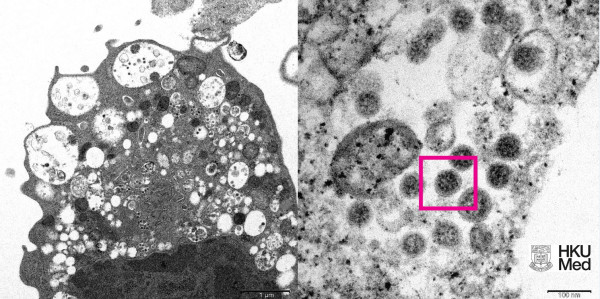

Σύμφωνα με το APA, επιστήμονες στον τομέα της υγείας, συμπεριλαμβανομένων παθολόγων και ιολόγων, κατάφεραν να λάβουν μια ηλεκτρονική μικρογραφία ενός κυττάρου (Vero E6) από το νεφρό ενός πιθήκου που μολύνθηκε με το συγκεκριμένο στέλεχος. Στη συνέχεια το Πανεπιστήμιο δημοσίευσε τις εικόνες χαμηλής και υψηλής μεγέθυνσης.

Αριστερά, είναι η ηλεκτρονική μικρογραφία χαμηλής μεγέθυνσης κυττάρου νεφρού πιθήκου (Vero E6) μετά από μόλυνση με την παραλλαγή Omicron SARS-CoV-2. Δείχνει κυτταρική βλάβη με διογκωμένα κυστίδια που περιέχουν μικρά μαύρα ιικά σωματίδια.

Δεξιά, είναι η ηλεκτρονική μικρογραφία υψηλής μεγέθυνσης μολυσμένου κυττάρου Vero E6. Δείχνει συγκεντρώσεις ιικών σωματιδίων με αιχμές σχήματος κορώνας στην επιφάνειά τους (κόκκινο πλαίσιο).